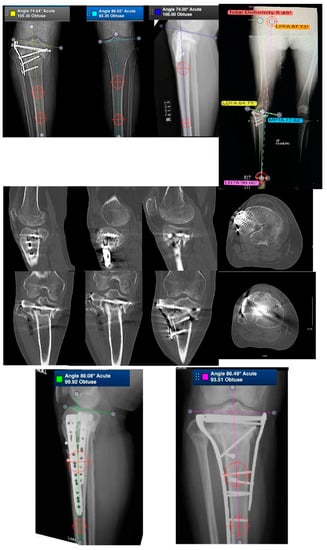

3.3. Tibial Shaft Malunion

Demographics and Complications